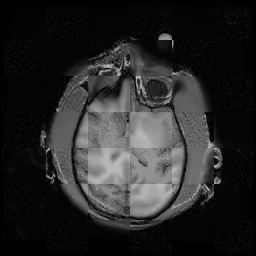

For each of the 10 subjects, we show checkerboard slices in each direction (1) before registration, first row; (2) after rigid->scaleversor->affine registration, second row; and (3) after BSpline registration, third row.

Note the unsuccessful BSpline registration result for Issac.

Issac

Issac is a good example of BSpline registration failure.

Ron noted, the reason might be that Issac had his mouth open, unlike most of the subjects registered successfully.